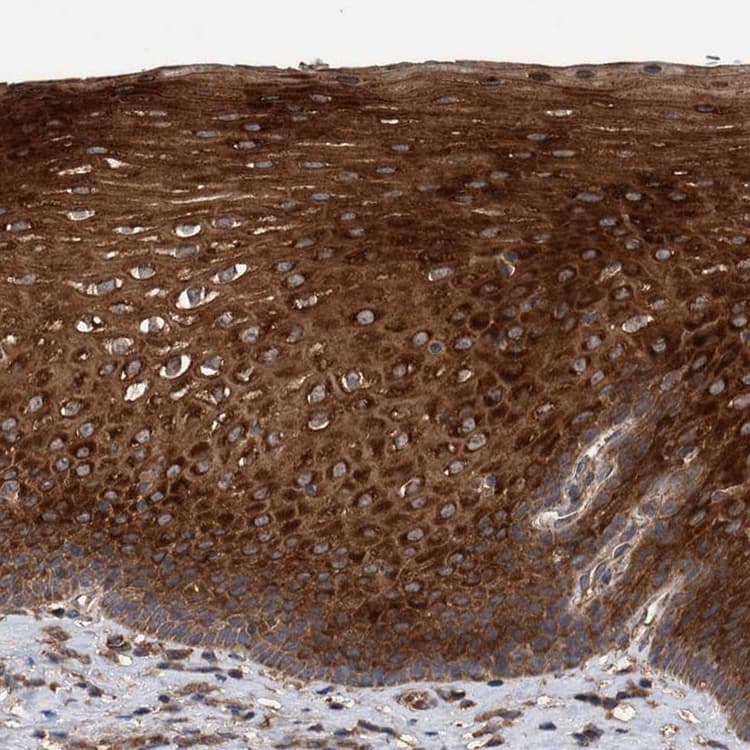

Rabbit Polyclonal TRIM16 antibody. Suitable for IHC-P, WB and reacts with Human samples. Cited in 1 publication. Immunogen corresponding to Recombinant Fragment Protein within Human Tripartite motif-containing protein 16 aa 50-250.

Applications IHC-P, WB

Species Reactivity Human